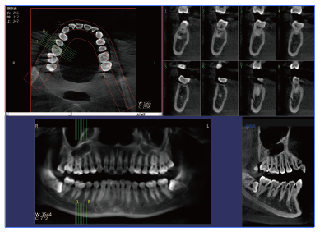

口腔cbct

PLX3000A口腔CBCT—普愛醫(yī)療